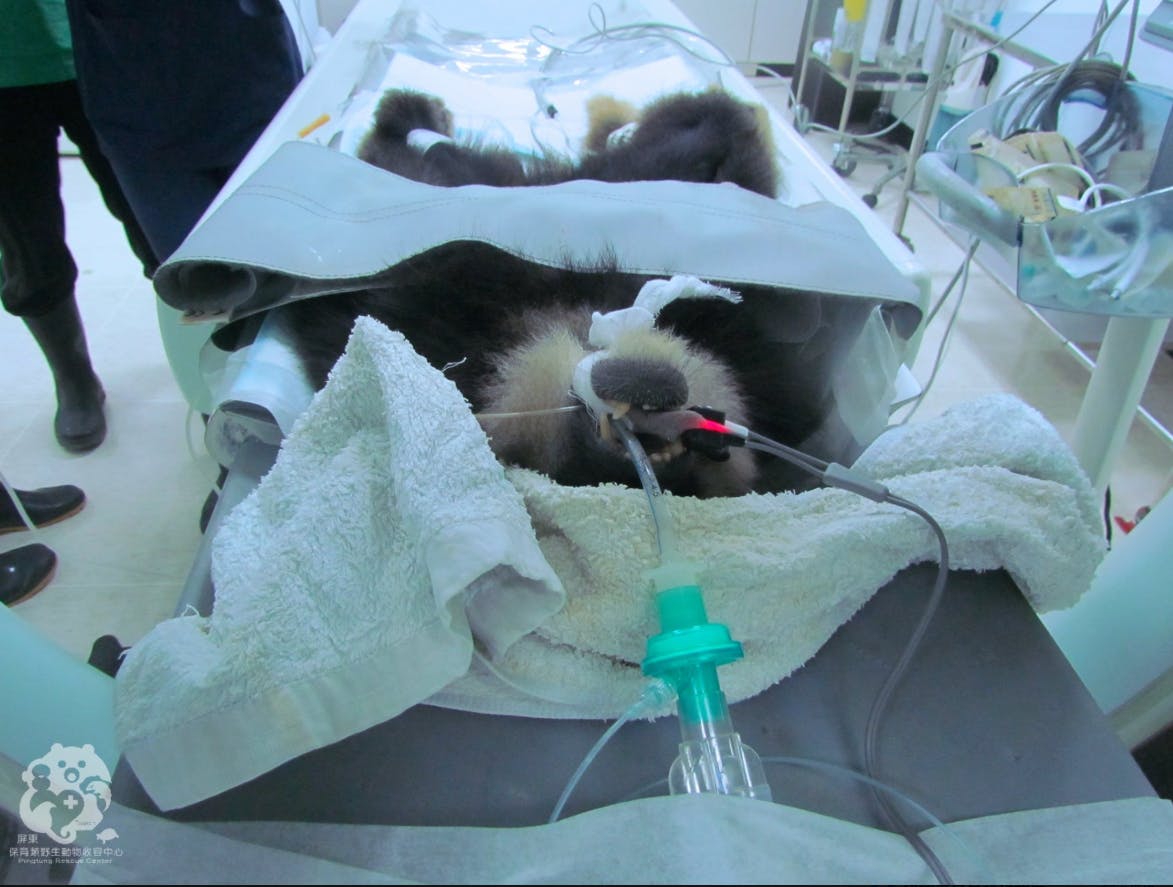

電腦斷層攝影(CT)利用X光穿透體內,再經由電腦重組呈現體內3D影像,實務上不是只有人類使用,屏東科技大學保育類野生動物收容中心與該校獸醫教學醫院合作進行了野生動物的拍攝。和在一般人在醫院的情況大大的不同,雖然畫面沒有拍到但因為是大工程動用人力不少,有紅毛猩猩、馬來熊、老虎、花豹(?)…等,乖乖的躺在床上其實還滿可愛的。

電腦斷層攝影(CT)利用X光穿透體內,再經由電腦重組呈現體內3D影像,實務上不是只有人類使用,屏東科技大學保育類野生動物收容中心與該校獸醫教學醫院合作進行了野生動物的拍攝。和在一般人在醫院的情況大大的不同,雖然畫面沒有拍到但因為是大工程動用人力不少,有紅毛猩猩、馬來熊、老虎、花豹(?)…等,乖乖的躺在床上其實還滿可愛的。